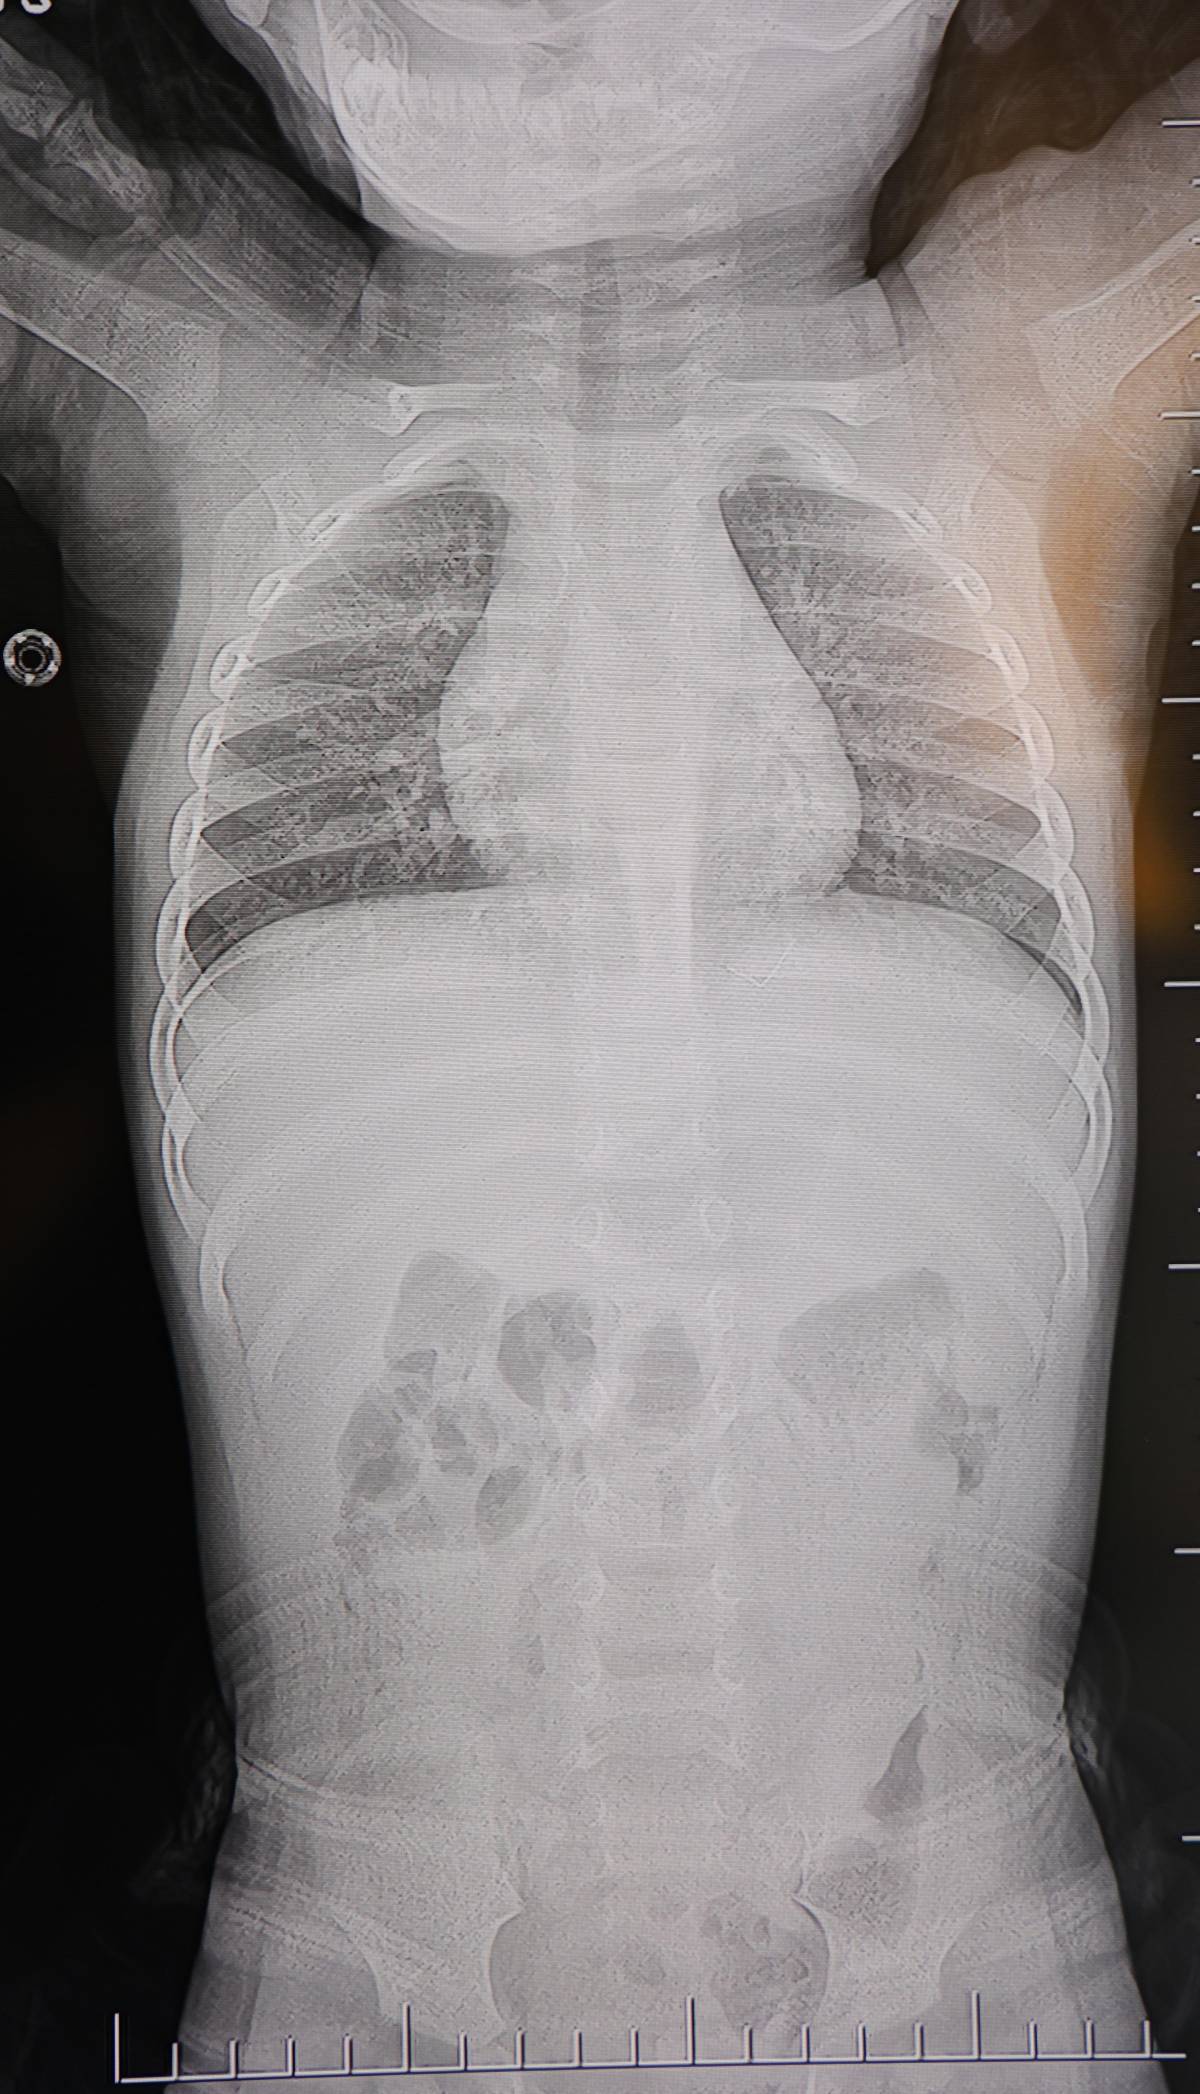

HG Hospital Beyin ve Sinir Cerrahisi Uzmanı Prof. Dr. İdris Altun tarafından yapılan detaylı tetkiklerde, yabancı cismin cilt altında, omurilik kanalına oldukça yakın bir bölgede bulunduğu belirlendi. Yapılan görüntüleme yöntemleriyle cismin, akciğer zarına doğru ilerlediği tespit edildi. Bu durum, olası risklerin daha da ciddi olabileceğini ortaya koydu.

Ameliyat sırasında çıkarılan yabancı cismin, ince zımba teline benzer metal bir tel olduğu belirlendi. Yaklaşık 2 santimetre uzunluğundaki bu telin, sırt bölgesinde zamanla ilerleyerek ciddi sağlık sorunlarına yol açabileceği kaydedildi. Cismin çıkarılmasının ardından bebeğin rahatladığı ve huzursuzluk belirtilerinin azaldığı gözlemlendi.

Operasyonu gerçekleştiren Prof. Dr. İdris Altun, konuya ilişkin yaptığı açıklamada, “Sırtında yabancı bir cisim olduğu söylenmiş ancak çıkarılamayacağı ve 8 yaşına kadar beklenmesi gerektiği ifade edilmişti. Bize başvurduğunda yaptığımız tetkiklerde, cilt altında, omurilik kanalına çok yakın ve akciğer zarına doğru ilerleyen bir yabancı cisim tespit ettik” ifadelerini kullandı.